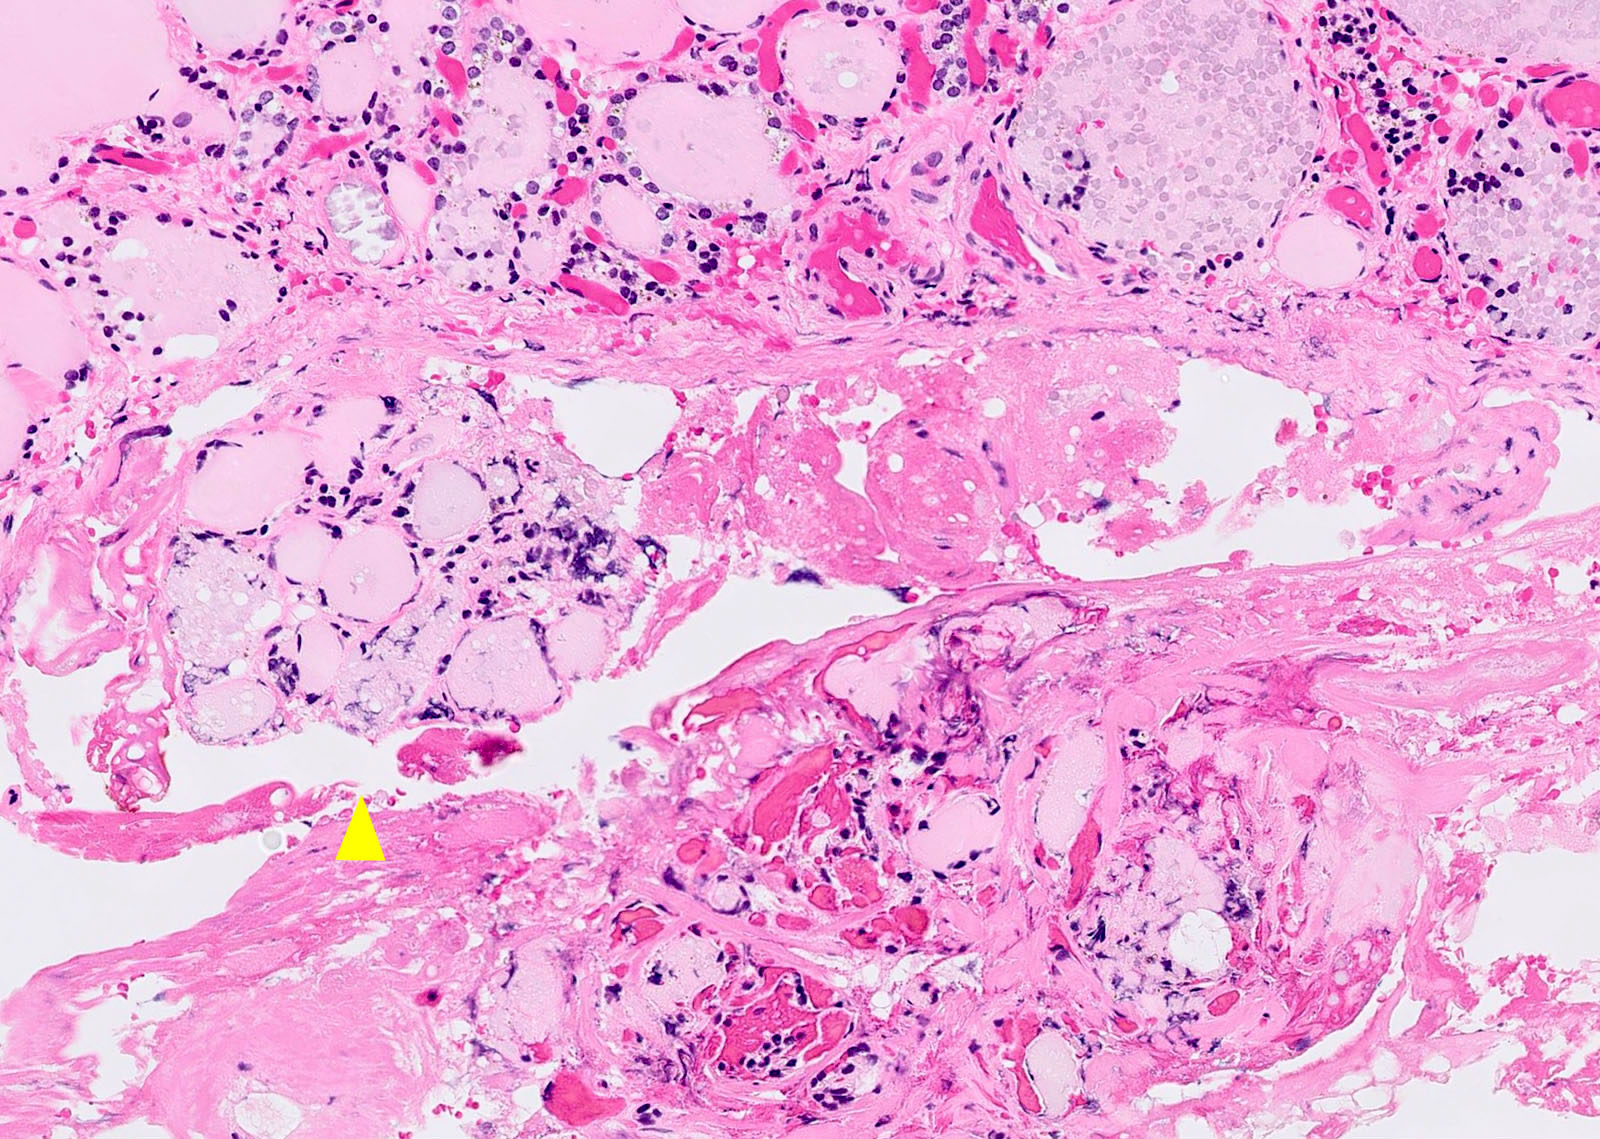

Microscopic (histologic) description

- Variable sized dilated follicles with flattened to hyperplastic epithelium

- Nodules may be present but without thick capsule

- Nodules with variable histological patterns: from colloid and microfollicular to hypercellular / microfollicular

- Secondary changes may be seen, including foci of fresh or old hemorrhage, rupture of follicles with granulomatous response, fibrosis, calcification and even osseous metaplasia

- Some of the cystically dilated follicles may show papillary projections (Sanderson polsters) that may mimic papillary carcinoma; however, they lack the nuclear features of papillary carcinoma

- Follicular carcinoma:

- Has vascular or capsular invasion, although multinodular goiter may have vascular invasion at periphery of nodule